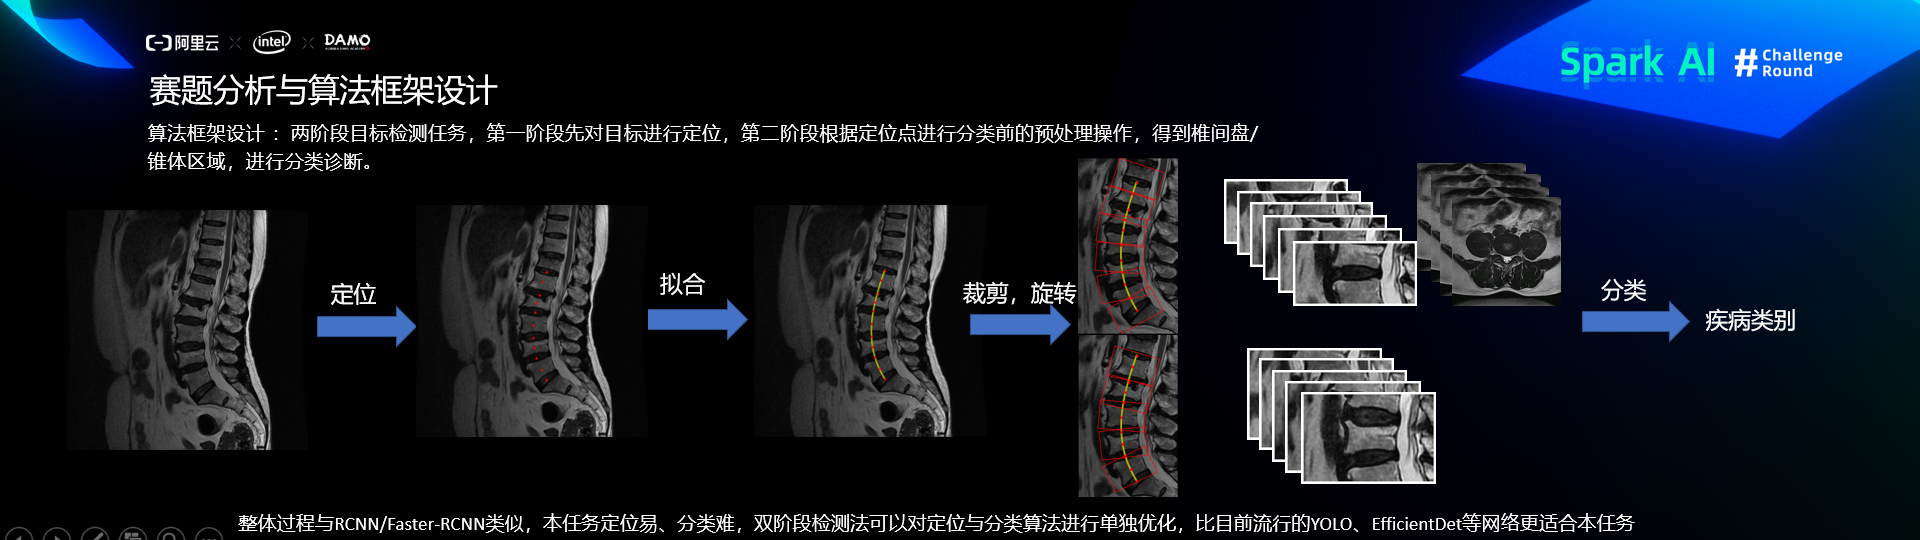

核心思路-算法框架设计

第一阶段:定位

预处理

定位网络